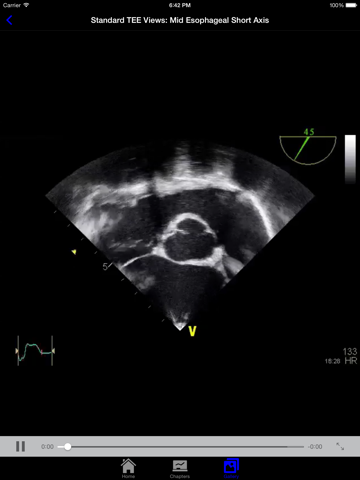

EchoSource (from the creators of ECGsource and CathSource) is a medical reference devoted exclusively to echocardiography. Developed by practicing cardiologists for both specialists and trainees in the field of cardiovascular disease, EchoSource offers the following content: * Searchable index of specialized topics including: History of Echocardiography Transthoracic Echo – Learning the Procedure Transesophageal Echo – Learning the Procedure Standard Transthoracic Echocardiography Views Standard Transesophageal Echocardiography Views Hemodynamics: Doppler Overview Hemodynamics: Color Flow Imaging Hemodynamics: Transvalvular Gradients Hemodynamics: Intracardiac Pressures Hemodynamics: Cardiac Flow & the Continuity Equation Hemodynamics: Proximal Isovelocity Surface Area (PISA) Left Ventricle: Systolic Function Left Ventricle: Diastolic Function Valvular: Aortic Stenosis Valvular: Aortic Regurgitation Valvular: Mitral Stenosis Valvular: Mitral Regurgitation Valvular: Pulmonic Stenosis Valvular: Pulmonic Regurgitation Valvular: Tricuspid Stenosis Valvular: Tricuspid Regurgitation Valvular: Prosthetic Valves Clinical Disorder: Aortic Dissection Clinical Disorder: Atrial Septal Defect Clinical Disorder: Constrictive Pericarditis vs. Restrictive Cardiomyopathy Clinical Disorder: Hypertrophic Cardiomyopathy Clinical Disorder: Intracardiac Masses - Endocarditis & Vegetations Clinical Disorder: Intracardiac Masses - Thrombus Clinical Disorder: Intracardiac Masses - Tumors Clinical Disorder: Pericardial Effusion Clinical Disorder: Pseudoaneurysm Clinical Disorder: Pulmonary Artery Hypertension Clinical Disorder: Subaortic Membrane Clinical Disorder: Ventricular Septal Defect * Searchable database consisting of more than 90 figures, images, and echocardiography videos of both common and rare findings in the field of echocardiography EchoSource provides a detailed overview of clinical disorders and their evaluation using echocardiography, incorporating educational figures and videos as well as reviews of pertinent medical literature. Whether you are a beginner just learning standard echocardiography imaging views, or a practicing clinician needing a quick reference to guideline-based echocardiographic criteria for diagnosing the severity of valvular heart disease, EchoSource is the ideal application to assist you.

Clinical disorder videos freeze-frame to point out the echo findings. Figures are detailed. Best pocket reference that I have found regarding echo criteria for severity of valvular heart disease and diastolic function parameters. Other reviewer commented on PSAX base view being mislabeled, but it is labeled correctly. Have not come across any inaccurate info. Strongly recommend.